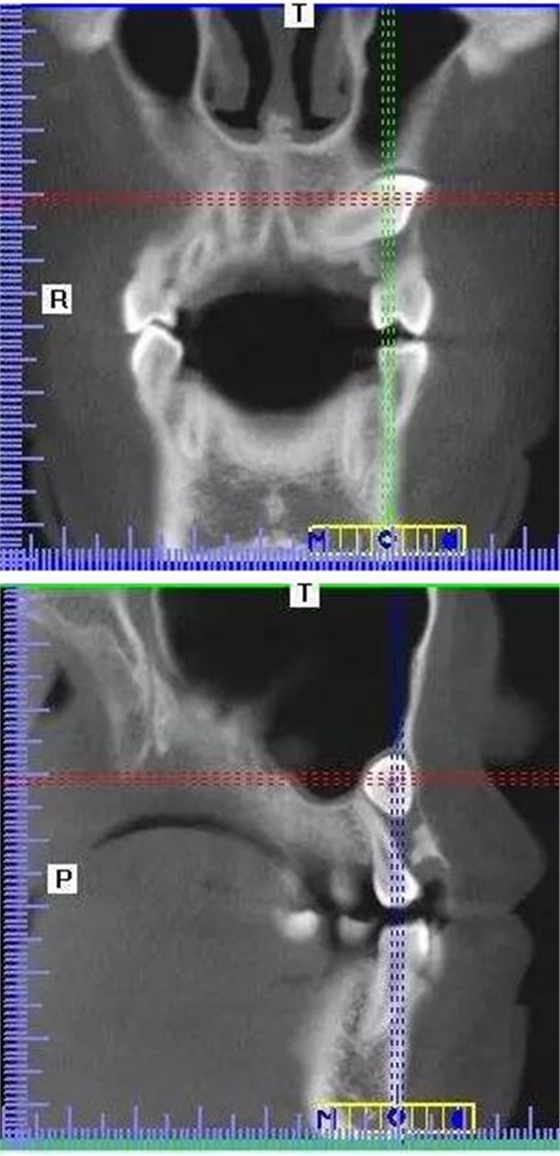

本案:患兒,女,14歲,因牙齒矯正來(lái)院,檢查見(jiàn)83滯留,43未見(jiàn)萌出,拍片發(fā)現(xiàn):43埋伏阻生于31、41、42根尖下方,按照正畸診療計(jì)劃,擬行43拔除術(shù)。

CBCT顯示